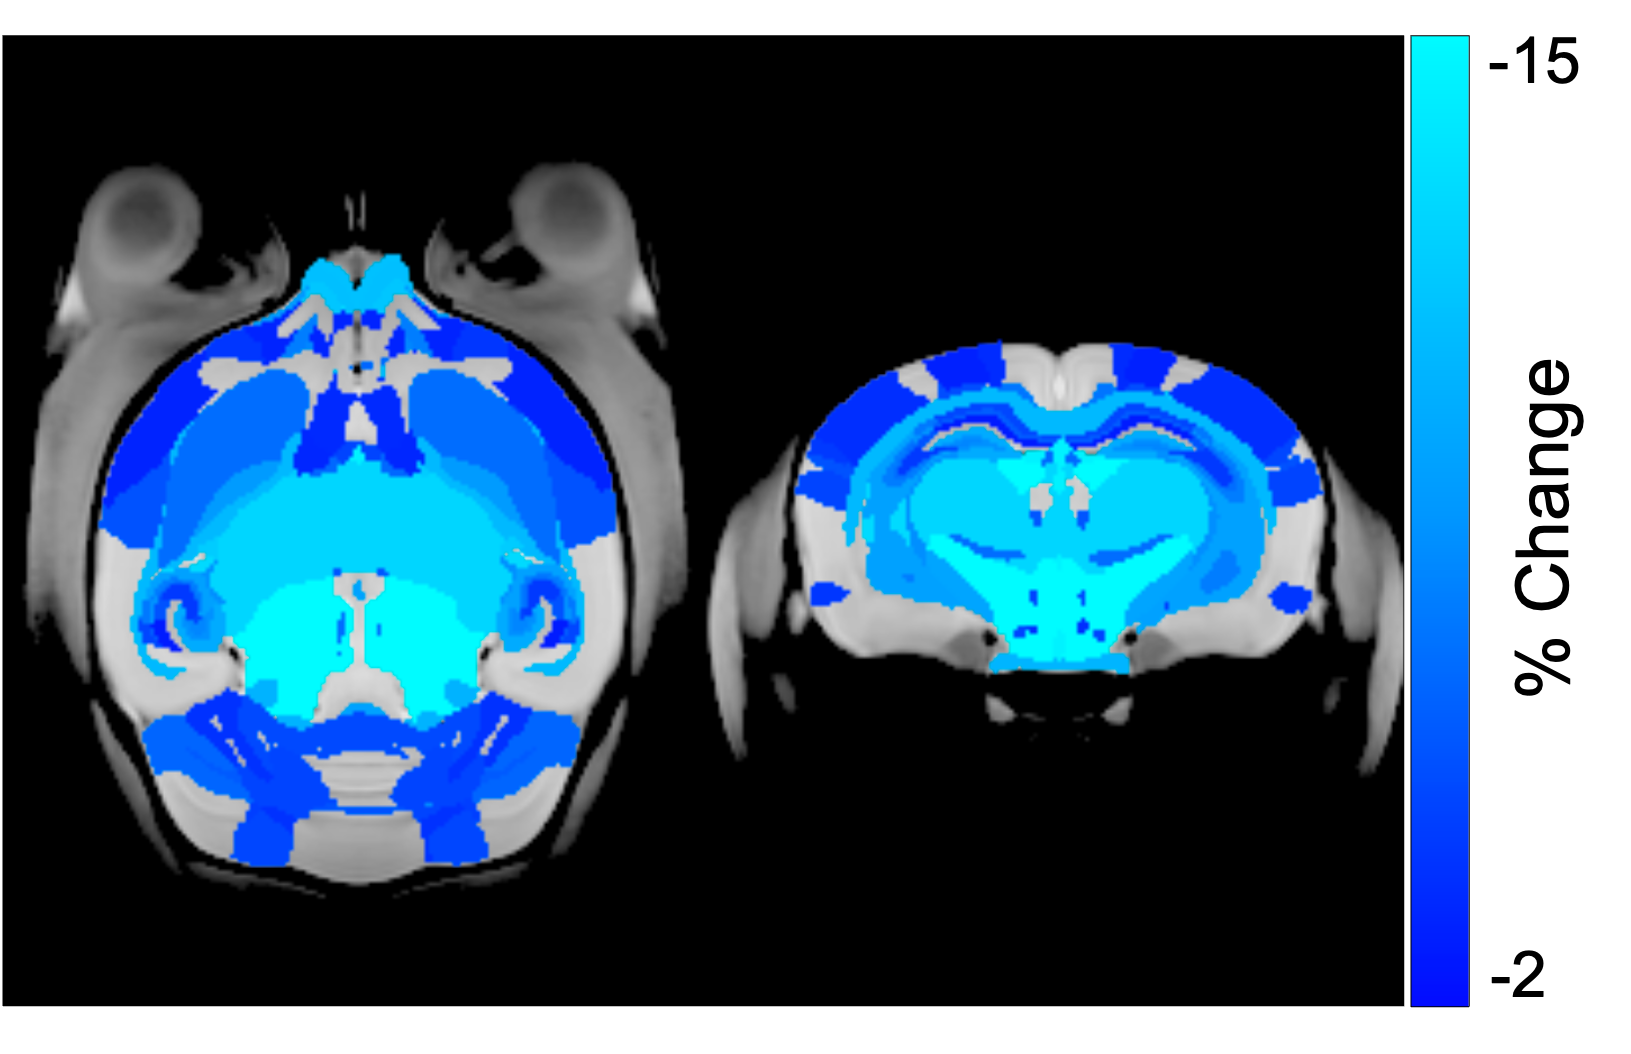

CRT induced widespread brain volume loss (Figure 2). Figure 3 shows the change in the radiation-induced deficit attributed to the four sex genotypes in Ccl2-/- mice at P98. The most prominent mitigation of radiation-induced volume loss occurred in mice with both XY- and Sry. XY and XX Sry Ccl2-/- mice exhibited partial recovery in several structures, such as the hippocampus (Figure 4), hypothalamus, thalamus, pons, midbrain, pituitary gland, and medulla. Ccl2-/- mice with an XY Sry genotype appeared to have the greatest overall brain volume recovery at P98, including the hippocampus (Figure 5).

Figure 2: Neuroanatomical maps showing volume deficits in the wildtype mouse brain after 7Gy cranial irradiation at P16. Coloured regions show brain structures with a significant volume deficit detected (FDR<10%). Brain volume deficits are observed in both cortical and subcortical regions.